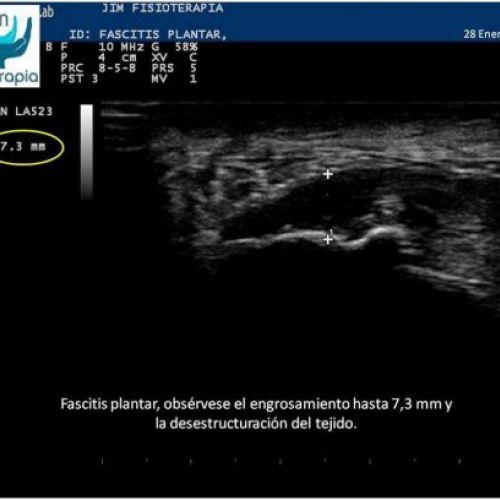

Tratamiento de fascitis plantar con EPI®

Terapia de electrólisis percutánea intratisular EPI® para el tratamiento de la fascitis plantar.